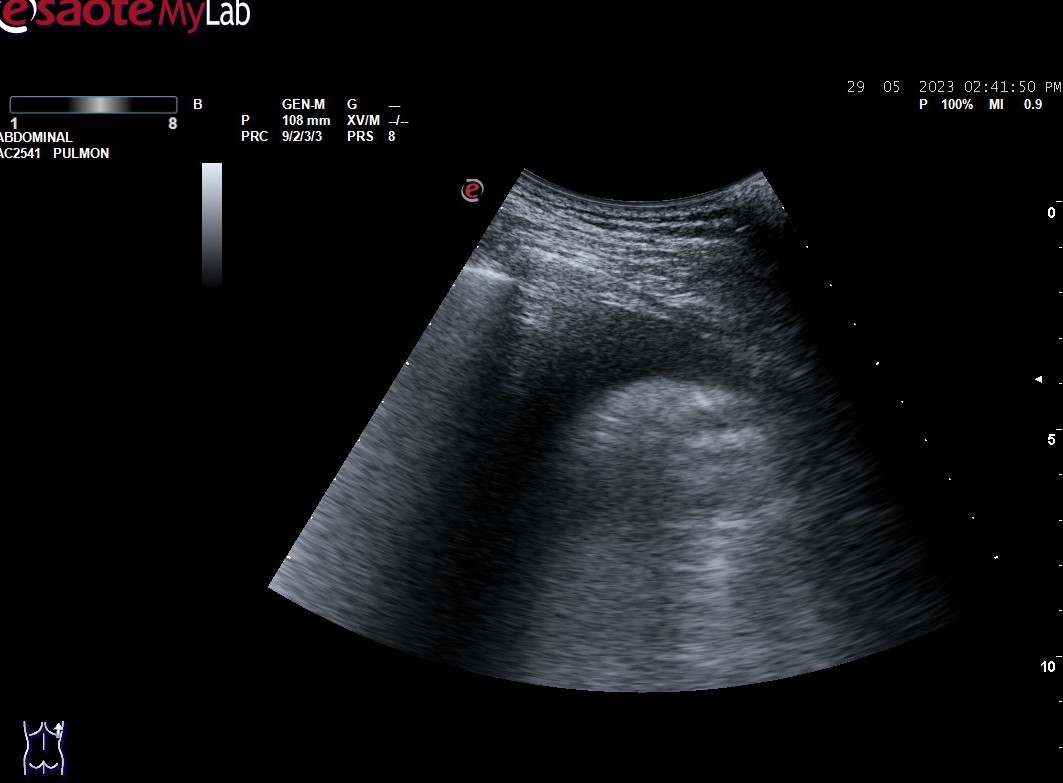

Hallazgos ecográficos: derrame pleural bilateral y abundantes líneas B (más de 3 por espacio intercostal) en ambos 1/3 medios inferiores bilaterales (adjuntamos imágenes).

En la ecografía pulmonar observamos unos patrones ecográficos (normal, deslizamiento pleural, líneas A, líneas B, derrame pleural y consolidación pulmonar). Realizando una serie de preguntas dicotómicas sobre estos patrones ecográficos se establece un algoritmo (protocolo BLUE) que permite establecer con alta sensibilidad y especificidad la causa de la disnea mediante un árbol de decisión.

Aplicando dicho protocolo establecemos un diagnóstico ecográfico de presunción de Edema Agudo de Pulmón/Insuficiencia cardíaca.